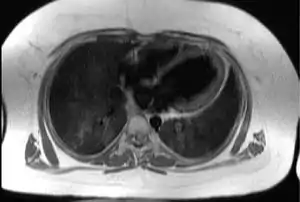

| دید بالایی-پایینی از سینهٔ انسان در محل قرارگیری قلب که بافت چربیِ تحتجلدی و اپیکاردیال (سفیدرنگ) را در بیمار مبتلا به «سندرم آلستروم» نشان میدهد و در نتیجه میتوان دریافت که چرا انجام اکوکاردیوگرافی قلب در این بیماران مشکل است. | |